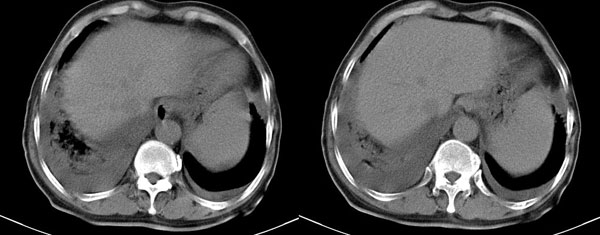

心衰致双侧胸腔积液,右肺下叶肺水肿,腹水。

原来是下腔静脉,长见识了,谢谢!

理论固然重要,但是,既然有人考虑肺不张,那么,哪一段?支气管分叉层面图片没有提供,因此,并不能就此诊断,如果由于腔静脉压迫引起肺通气功能障碍,好像比较少见